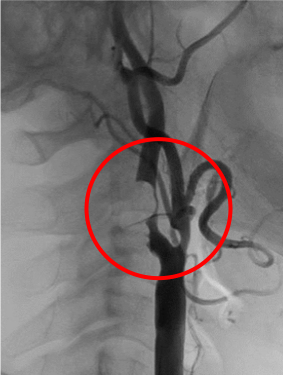

頚動脈高度狭窄

術前の頚動脈造影写真です。〇内に頚動脈狭窄が見られます。

造影されていない部分にはプラークが付着しています。

頚動脈ステント留置術後の造影写真です。狭窄は改善しています。